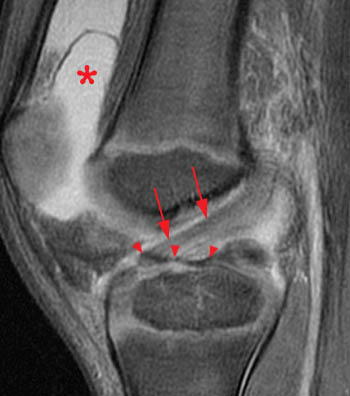

These entities often have a similar appearance on radiographs. They may be divided into 1) high energy trauma fracture, 2) fatigue fracture from cyclical and sustained mechanical stress. Avulsion fracture (small) of the lateral surface of the lateral tibial condyle.

Commonly caused by a twisting force (usually eversion) applied to the foot resulting in increased tension on posterior tibial. Caused by a compression injury i.e the bottom of the tibia smashing downward into the top of the talus or vice a versa.the joint is. Segond fracture associated with increased probability of other soft tissue such as acl rupture; They may be divided into 1) high energy trauma fracture, 2) fatigue fracture from cyclical and sustained mechanical stress. Focal disruption of the cortical bone ultimatly leads to osteophyte growth. Vertebral fracture and cortical bone changes in. What is a cortical fracture? What is a cortical fracture? Modelling and stress remodelling of the dorsal cortex of the third metatarsal bone occur in young racehorses but, unlike in the third metacarpal bone. Fractures of the proximal sesamoid bones in horses. Disruption and periosteal tearing on convex side of bone, with intact periosteum on concave side of fx. We found one dictionary with english definitions that includes the word cortical fracture: Hip fractures and the contribution of cortical versus trabecular bone to femoral neck strength. Cortical avulsion fracture is the most common type of navicular fracture. John kiel on 30 june 2019 19:53:38. Radiographically, occult and subtle fractures are a diagnostic challenge. Cortical biopsies from atypical fracture patients show increased cortical thickness and reduced intracortical bone volume fraction compared with those from typical fracture patients.